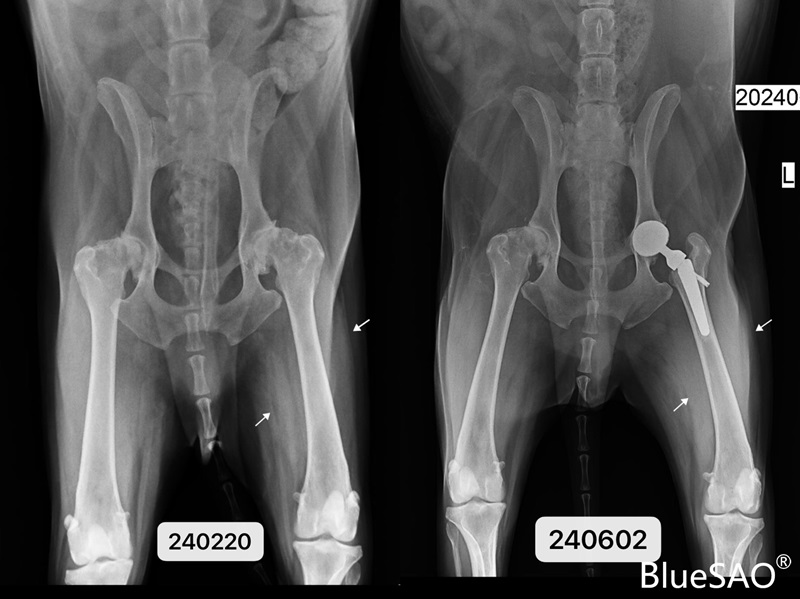

三个月前,13岁的萨摩Rocky因双侧髋关节发育不良,导致后肢无力,起立缓慢。我们使用BlueSAO Bionic仿生髋关节系统为它成功进行了左侧的髋关节置换手术。

三月前手术X光片对比图: